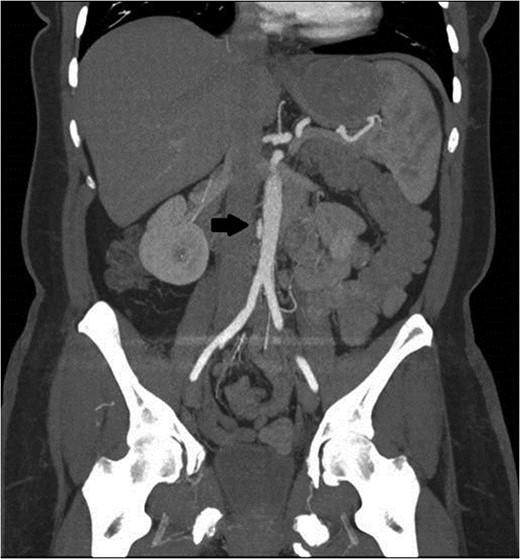

A follow-up CT scan was obtained 3 months later. At the location of the previous aortic abnormality, there was a 3 × 1 cm pseudoaneurysm that had formed and could now be clearly seen (Figs 2 and 3). The patient was asymptomatic.

Black arrow pointing to pseudoaneurysm with enhancing flow outside of the aortic lumen.